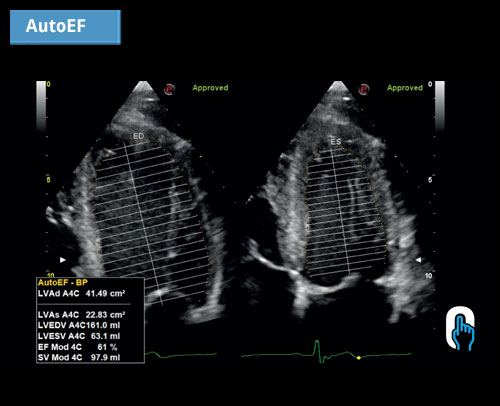

AutoEF: automatická detekce hranice endokardu zrychluje měření EF a zjednodušuje každodenní rutinu.